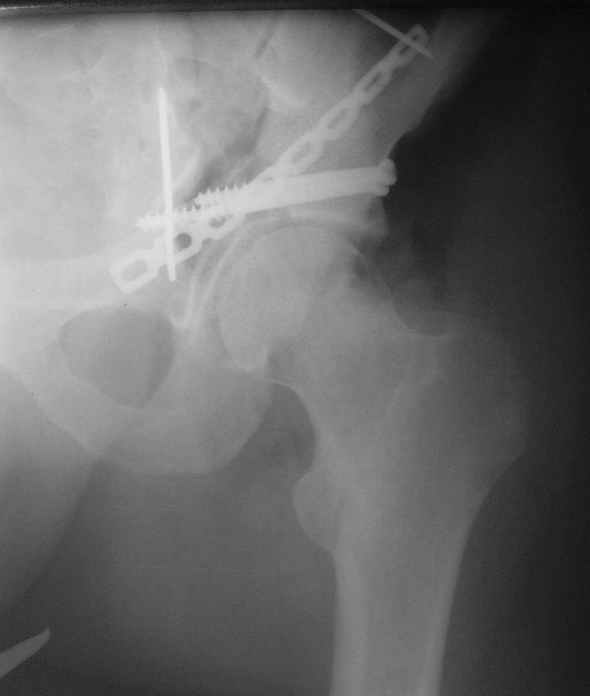

Не дождавшись советов, в понедельник прооперировал больного, заняло времени..., но все сделал в один этап: сначала фиксировал ипсилатеральный перелом бедра и шейки реконструктивным гвоздем Smith&Nephews, потом из расширенного илеофеморального доступа фиксировал перелом крыла подвздошной кости тягловым винтом, нейтрализующей пластиной заднюю колонну, и тягловыми винтами 3,5 мм переднюю колонну.

перелом крыла правой подвздошной кости, перелом обеих колонн вертлужной впадины, двусторонний перелом лонных костей (С2.2) повреждение передних связок правого крестцово-подвздошного сочленения,

ипсилатеральный перелом шейки и диафиза бедра.

К сожалению, набора для ретроградного или антеградного реконструктивного штифтования в операционной нет, поэтому доставка заняла н-ное время. Вопрос, который возник у меня- по поводу оптимальной тактики хирургии: вся фиксация в один этап из расширенного доступа или последовательно сначала бедро и позже реконструкция впадины, комбинированный доступ к впадине отдельно к передней и задней колоннам или из расширенного илеофеморального одного доступа. Все-таки решил остановиться на одноэтапном подходе и спустя 5 дней (как раз и наборы привезли) из расширенного илеофеморального доступа сначала фиксировал реконструктивным штифтом Smith&Nephews бедро и

шейку (благо перелом шейки 2 типа -относительно стабильный) затем фрагмент крыла подвздошной кости Lag screw, далее пластина на заднюю колонну и винты в переднюю колонну.(с размерами и направлением винтов ошибка вышла:-((, но интраоперационно у меня была полная уверенность , что винты *ушли* в лонную кость).

Еще раз спасибо за комментарии и готовность помочь с имплантами. Постоп картинки в приложении,